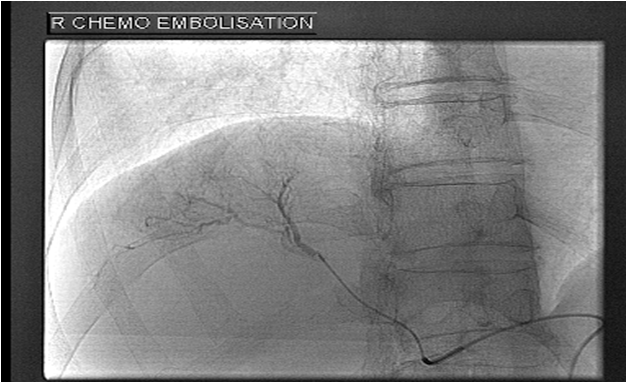

With better understanding of the disease pattern and the body’s requirements for liver function, various options for treatment of liver diseases and cancer must be available either as a single therapy or as a combination. Dr Chang is the Founding President of the Hepatopancreatobiliary Association of Singapore where in the early years of it formation, helped promote the integrated multi-disciplinary treatment of liver diseases. Such services available in GLAD Clinic and its associates include: Liver Transplantation Liver Resection Local ablative therapy (Radiofrequency, Microwave, Ethanol) TACE – Transarterial Chemoembolization Y90 Radioactive isotope embolization Systemic therapy e.g. Sorafenib